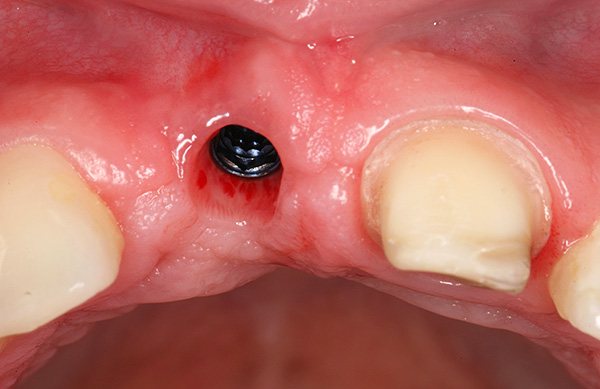

На фотографиях ниже показаны удаленные импланты:

После удаления подвижного импланта проводят процедуру комплексной подготовки лунки к следующей имплантации, которую могут осуществить уже через 1-2 месяца. Например, при значительной убыли костной ткани или близости к гайморовой пазухе может потребоваться наращивание кости челюсти под зубной имплант (операция синус-лифтинга).